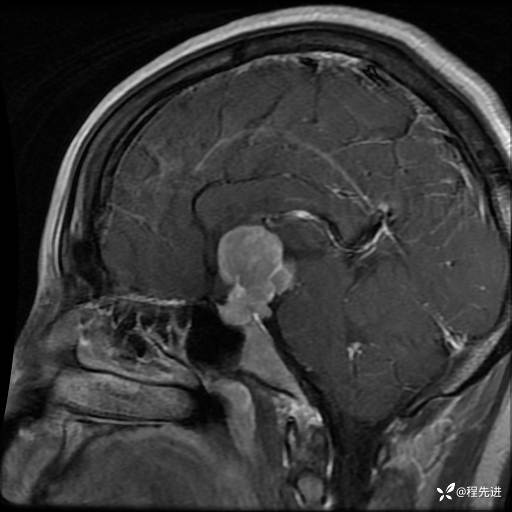

MRI平扫+增强:

T1+C: